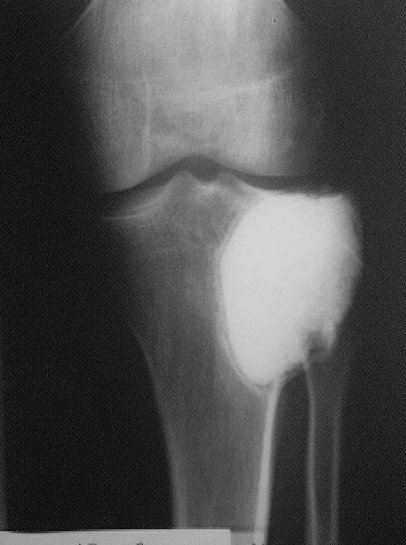

Около года назад больному 25 лет по поводу литической опухоли мыщелка б\б кости ( ОБК?)с выраженным болевым синдромом была произведенарасширенная открытая биопсия, экскохлеация опухоли.

В связи с неясностью диагноза до операции и отсутствия аллокости в тот момент интраоперационно было выполнено экспресс протезирование дефекта мыщелка акриловым цементом. Верхней стенкой дефекта была визуально неповрежденная суставная поверхность. Хрящевая пластина провисала - была выведена на уровень и "подперта" цементным спейсером. Больной осмотрен через год - ходит не хромая, сустав абсолютно спокойный, рентгенологически процедива опухоли нет. Хотелось бы услышать предложения по пластике дефекта - сроки, вид материала. Честно говорябоюсь трогать хрящ повторно.

Случай очень интересный! Увидеть бы снимки до операции. Можно обсудить состояние хряща "на цементе"-за счет чего он жив или там все-таки дефект? Щель сустава хорошая. Есть ли возможность проведения МРТ у больного?